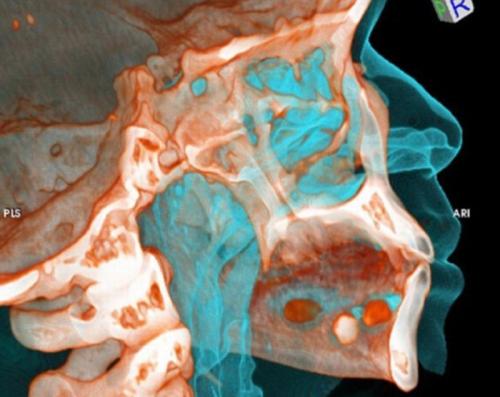

Рентгеновские снимки «лошадок» - людей, перевозящих небольшие партии наркотиков внутри своего тела. Если контейнеры с наркотиками раскрываются - человек умирает.

Пакетики с кокаином под языком.

9 пакетов кокаина.